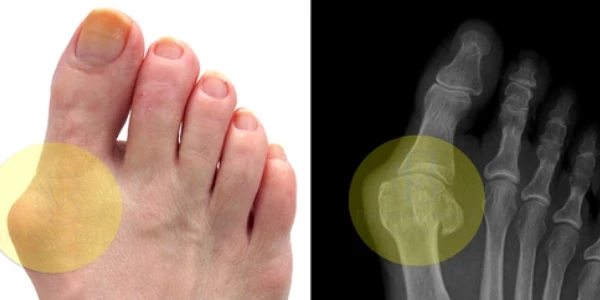

Косточки на больших пальцах – сильно выступающие и порой очень болезненные – явление довольно распространенное. Это заболевание под названием бурсит. Лечить бурсит можно и нужно, однако в некоторых случаях справиться с проблемой поможет только хирургическое вмешательство. Далее мы ответим на самые распространенные вопросы о косточках на больших пальцах ног и их коррекции.

Бурсит – это не нарост кости, как многие думают. На самом деле – это результат неправильного расположения сустава пальца. Сначала у основания пальца появляется выступ, а сам палец изгибается и становится под углом ко всем остальным. В результате механического воздействия суставная сумка воспаляется и увеличивается в размерах. Так формируются так называемые «косточки на больших пальцах».